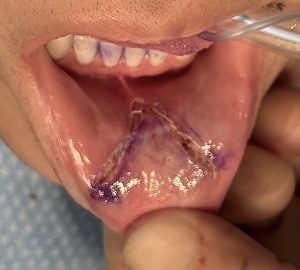

- Uses a V-shaped incision made on the inside (mucosa) of the lip (upper, lower, or both).

- The underlying mucosa is released and advanced outward toward the vermilion (the pink part of the lip).

- The incision is then closed in a Y configuration, effectively moving tissue forward.

This young female had lost volume in the center of the lower lip from a prior bony genioplasty procedure. She desired more central lower lip fullness.